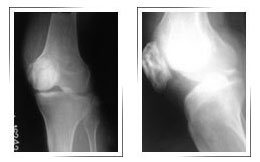

Before surgery X-ray

Before Surgery